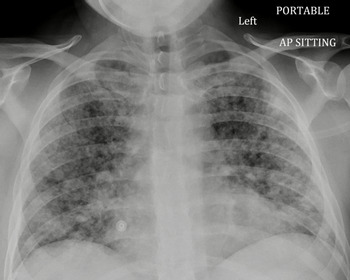

A 31-year-old male presented with a 2-year history of progressive headaches, nausea, vertigo, bilateral arm paresthesias, and blurry vision. His past medical history was unremarkable. A magnetic resonance imaging demonstrated an enhancing lesion of the posterior fossa and obstructive hydrocephalus. He underwent urgent suboccipital craniectomy and the surgical pathology was consistent with a WHO grade 4 medulloblastoma. After in-patient rehabilitation, the patient was discharged home on dexamethasone 4 mg twice daily (BID) with a plan for radiation followed by chemotherapy. Three weeks later, the dexamethasone dose was increased by the patient’s family physician to 8 mg BID. Three months after surgery, he presented acutely to the ED with a history of fever, chills, and dry cough. He had features of sepsis with tachypnea, tachycardia, and relative hypotension. His initial CXR was largely unremarkable and his oxygen saturation was normal on room air. He was started on broad spectrum antibiotics. Two days following his admission to the internal medicine team, he developed acute respiratory failure. Repeat CXR was most consistent with acute respiratory distress syndrome ( Figure 2). He was transferred to the ICU for intubation due to profound hypoxemia. BAL was positive for PJP. He was started on high-dose TMP/SMX and steroids. He deteriorated despite lung protective ventilation, neuromuscular blockade, lung recruitment maneuvers, prolonged prone positioning, and inhaled epoprostenol. Comfort measures were instituted and he passed away peacefully in accordance with his previous wishes.

Figure 2: AP chest radiograph demonstrating diffuse, bilateral, and nodular parenchymal opacities.